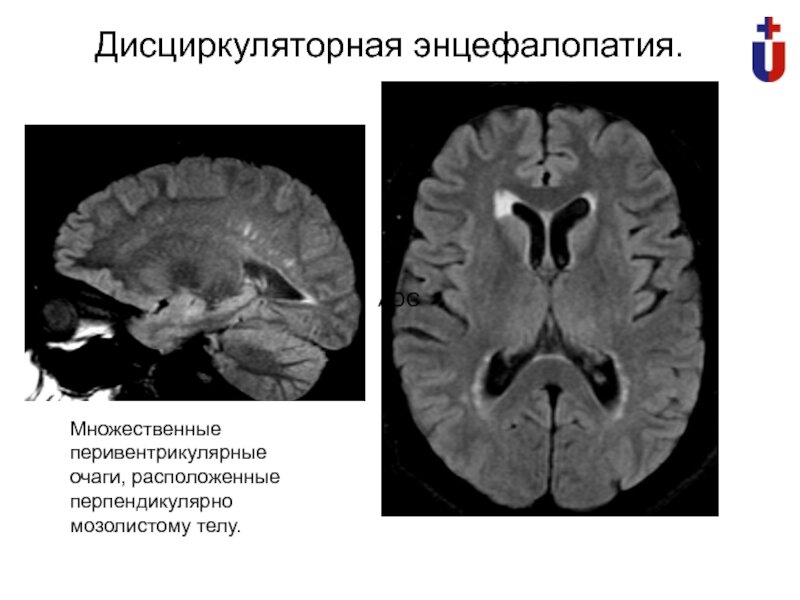

Дисциркуляторная энцефалопатия или ДЭ

Дисциркуляторная энцефалопатия (ДЭ) - это заболевание, которое связано с нарушением кровоснабжения мозга и может привести к различным неврологическим и психическим расстройствам. Она часто возникает у пожилых людей, но может проявляться и у молодых людей.

При ДЭ мозг не получает достаточно кислорода и питательных веществ, что приводит к постепенному ухудшению его функций. Симптомы ДЭ могут быть различными и включают в себя головокружение, шум в ушах, плохую координацию движений, забывчивость, нарушение речи и мышления, а также депрессию и тревожность.